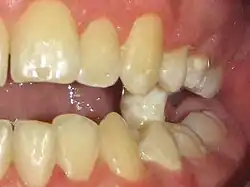

- Béance - Il existe un espace vertical libre entre les dents en intercuspidation maximale volontaire. L'espace résulte des puissantes pulsions linguales centrifuges (interpositions linguales), responsables de l'arrêt prématuré de l'éruption (dents trop petites) ou de versions dentaires. Les incisives peuvent ainsi soulever la lèvre supérieure, ou éversions vers l'avant (incisives « en chasse-neige »). La béance canine induit le bruxisme des dents voisines (usures prématurées). L'occlusion des arcades dentaires dévoile une supraclusion antérieure, ou large recouvrement vertical des incisives inférieures par les dents supérieures ;

- Infraclusion organique[6] - La hauteur clinique des dents est verticalement « trop petite » au niveau des prémolaires et molaires (Vidéo2) et l'Espace libre est « trop grand », ce qui induit des malocclusions, des dysfonctions, des fatigues musculaires (gènes, douleurs, crampes), une égression du bloc incisivo-canine inférieur (éruption exagérée) et des béances dentaires (absence de protection canine, bruxisme et dents cuspidées plates). Une réduction de 3 à 4 mm de la distance interocclusale implique une forte réduction de l'activité des muscles masticateurs[36] ;

- Égression relative du bloc incisivo-canin inférieur[43], visiblement accentuée par une infraclusion organique[6] des dents cuspidées inférieures (prémolaires et molaires) (Fig.11).

- Toutes les dents permanentes, « libres d'un REIOR », se retrouvent « suspendues dans le vide » : elles reprennent une éruption dento-alvéolaire passive. Ceci confirme le ralentissement et l'arrêt du processus d'éruption buccale par les pressions verticales de la langue lors de ses 1500 à 2000 interpositions quotidiennes entre les arcades dentaires (déglutition infantile, déglutition atypique).

- En deux ou trois mois, cette éruption passive se poursuit jusqu'à l'occlusion des deux arcades dentaires antagonistes. Le procès alvéolaire accompagne le mouvement dentaire : il n'y a aucun signe de déchaussement, ni égression dentaire. On profite de cette phase mouvante pour résoudre les malpositions, dentaires (diastème ou espace entre deux dents) ou basales (articulé croisé des maxillaires).